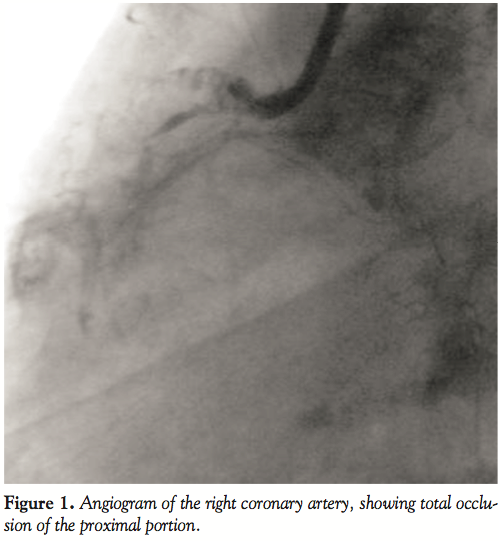

Case Report. A forty-year-old, male, chronic smoker, non-hypertensive, and non-diabetic patient presented to us with Canadian Cardiological Society class III angina of 1-month duration following an acute inferior wall myocardial infarction (MI) for which he was not thrombolyzed (having presented beyond the window period). Echocardiogram showed severe hypokinesia of the inferior wall with normal contractility of all the other myocardial segments and a global left ventricular ejection fraction of 50%. The patient was taken up electively for coronary angiogram and possible myocardial revascularization. Prior to angiogram, the patient was given a loading dose of clopidogrel and aspirin. Angiogram of the left system revealed an ectatic left anterior descending artery (LAD) with TIMI-3 flow, a normal left circumflex artery (LCX) and retrograde filling of the posterior descending artery (PDA) and posterior left ventricular (PLV) branches of the RCA from the left system. Angiogram of the right system showed total occlusion of the proximal RCA (Figure 1). After giving a bolus of abciximab (0.25 mg/kg body weight bolus